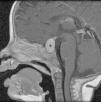

La histiocitosis de células de Langerhans (HCL) es una enfermedad rara caracterizada por la acumulación en los tejidos de células dendríticas anómalas similares a las células de Langerhans. La presentación clínica varía desde la aparición de una lesión ósea única hasta la afectación multisistémica. La implicación del sistema nervioso central (SNC), manifestada como diabetes insípida secundaria a afectación hipofisaria, es conocida desde la descripción original de la enfermedad. En la actualidad, se diferencian 2 tipos de lesiones del SNC: las lesiones seudotumorales, con infiltración por las células de Langerhans, cuya manifestación más frecuente es la infiltración hipofisaria, y otras, de más reciente descripción, las lesiones neurodegenerativas del SNC, asociadas a deterioro neurológico, que constituyen una complicación de la enfermedad de causa discutida. Nuestro objetivo es describir las manifestaciones radiológicas de la HCL en el SNC en los pacientes pediátricos.

Langerhans cell histiocytosis (LCH) is a rare disease characterized by the accumulation within tissues of anomalous dendritic cells similar to Langerhans cells. The clinical presentation varies, ranging from the appearance of a single bone lesion to multisystemic involvement. Central nervous system (CNS) involvement, manifesting as diabetes insipidus secondary to pituitary involvement, has been known since the original description of the disease. Two types of CNS lesions are currently differentiated. The first, pseudotumoral lesions with infiltration by Langerhans cells, most commonly manifests as pituitary infiltration. The second, described more recently, consists of neurodegenerative lesions of the CNS associated with neurologic deterioration. This second type of lesion constitutes a complication of the disease; however, there is no consensus about the cause of this complication. Our objective was to describe the radiologic manifestations of LCH in the CNS in pediatric patients.